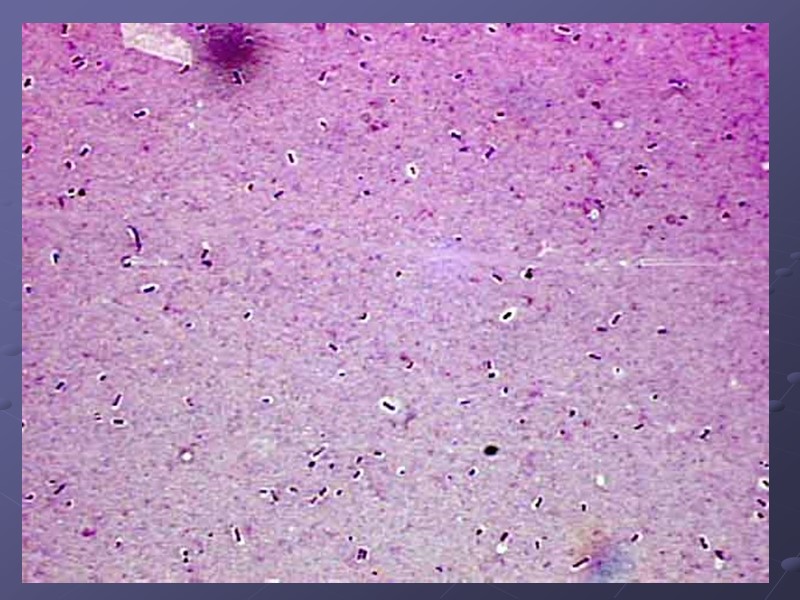

Синегнойная палочка: морфологические свойства Грамотрицательные, мелкие или средние палочки, не образующие эндоспору и макрокапсулу, подвижные (1-2 полярных жгутика), беспорядочно располагающиеся в мазке; образуют слизь

Ацинетобактерии Грамотрицательные полиморфные палочки В мазке – пары, короткие цепочки Множественная устойчивость к антибиотикам